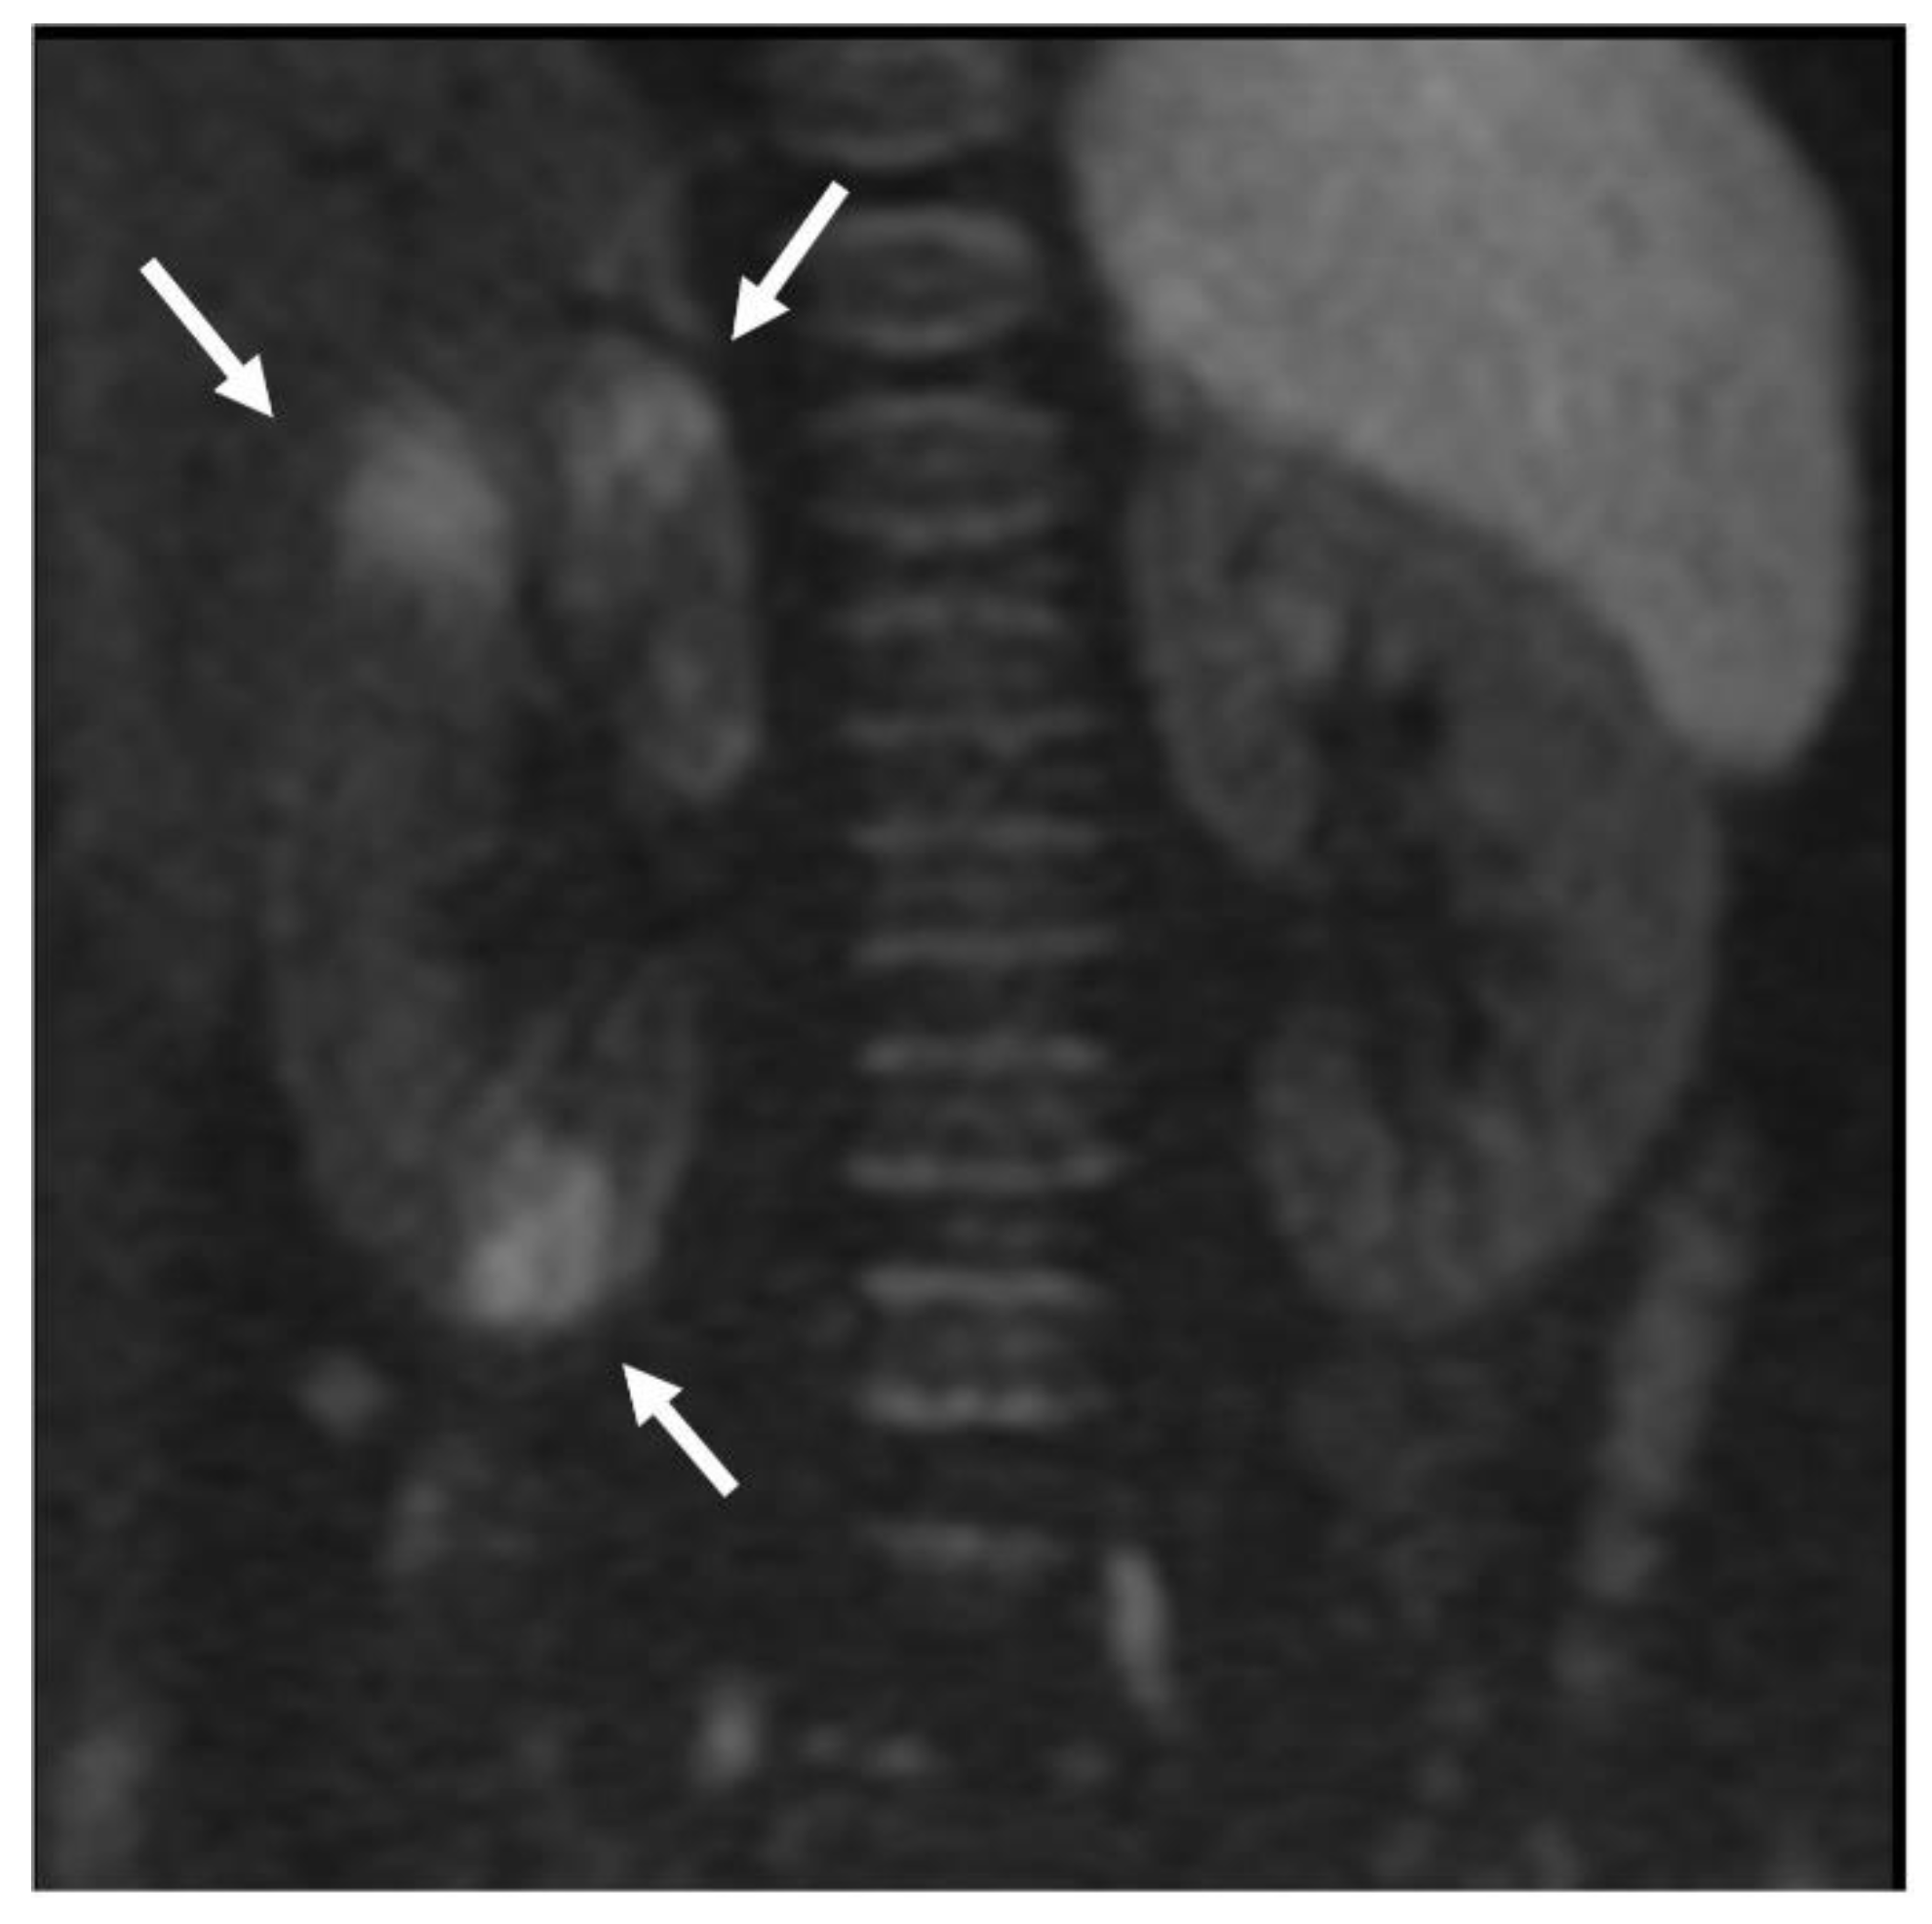

- Focal parenchymal areas with restricted diffusion;

- Seat, number, and mono- or bi-laterality of the focal renal lesions.